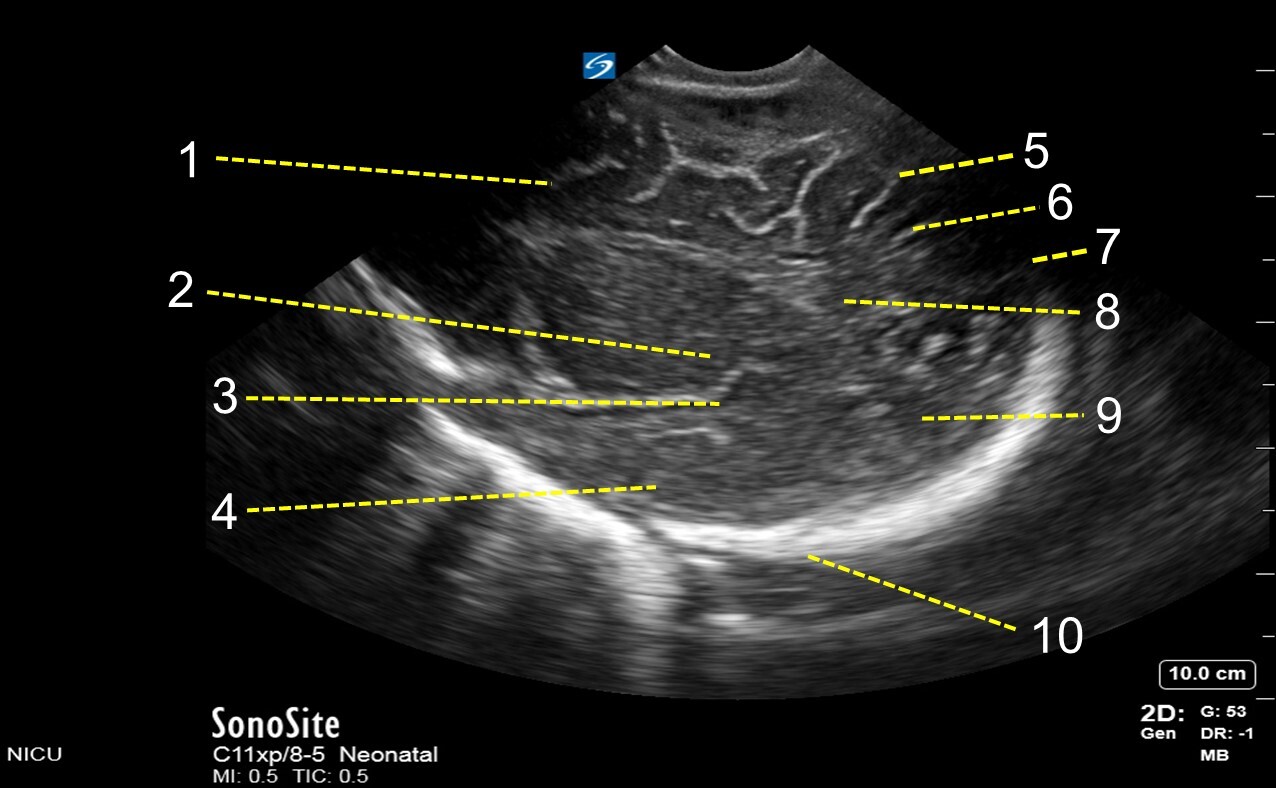

1. Frontal Lobe

2. Insular Area

3. Sylvian Fissure

4. Temporal Lobe

5. Precentral Sulcus

6. Central Sulcus

7. Postcentral Sulcus

8. Parietal Lobe

9. Occipital Lobe

10. Skull